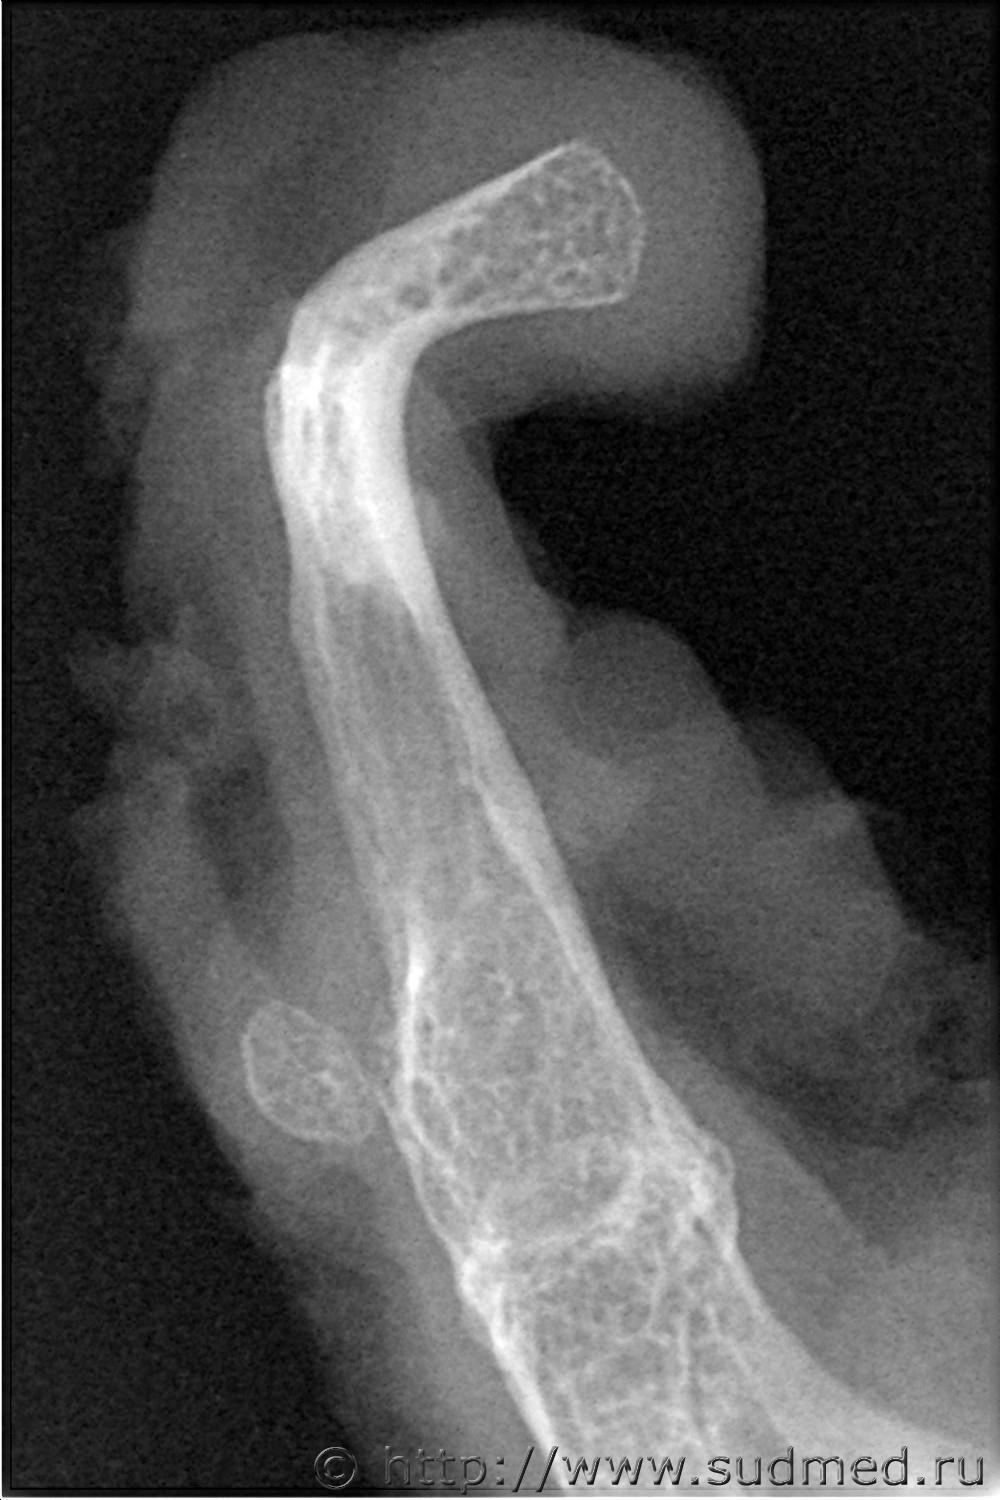

Подъязычная кость при повешении. Правда без повреждений.

1. Рентгенограмма правого большого рога.